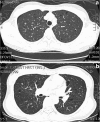

Pneumothorax in pulmonary lymphangioleiomyomatosis (LAM) with tuberous sclerosis complex (TSC) is a difficult condition to manage. Video-assisted thoracoscopic surgery (VATS) may play a role in diagnosis and treatment of this situation. We present a case of right recurrent pneumothorax due to LAM with TSC in whom VATS was performed for pathological diagnosis and mechanical pleurodesis. The unique presentation of LAM in TSC was also discussed.